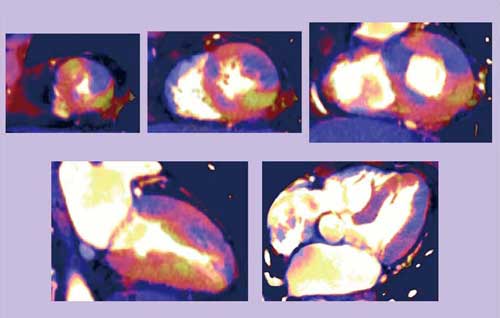

●Case4:高心拍数への対応

65歳,女性,労作時胸痛,撮影時心拍数(HR)が75bpmの症例である。HRが高いため100kVと140kVの合成画像再構成がうまくいかず,ヨード強調マップ(画像)では数値エラーが虚血のように見えている(図4)。われわれの経験では,HRが上がると,アーチファクトにより画質が劣化することが明らかになった(図5)。時間分解能の不足や低電圧(100kV)側のノイズが原因となり,heartPBVソフトウェアでの再構成エラーに遭遇することも多い。

時間分解能は128スライスのDSCT「SOMATOM Definition Flash」で改善されていくはずだが,低電圧側のノイズの低減については現在,われわれとシーメンス社の共同研究による3D Denoise filterの開発が行われている。

DEイメージングによる遅延造影は,内膜側に限局した遅延造影の範囲はきれいに描出可能だが,100kVと140kVの合成不良によるアーチファクト領域も出るため, 今後,時間分解能の改善や3D Denoise filterの応用が必要と考えられる。